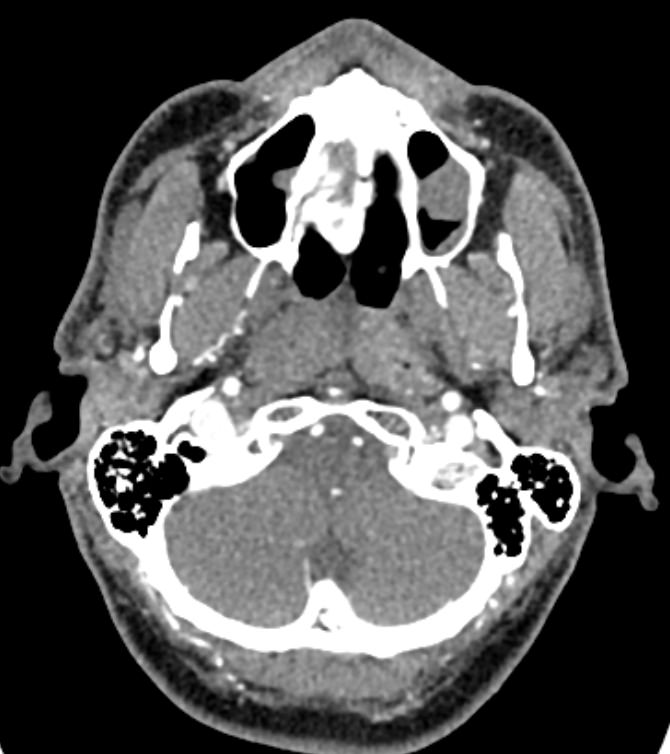

КТ сосудов шеи и головного мозга (КТ-ангиография) позволяет комплексно оценить состояние брахиоцефальных артерий и сосудов головного мозга, включая Виллизиев круг, передние средние и задние мозговые артерии. С помощью КТ-ангиографии можно выявить аномалии развития сосудов (в том числе, аневризмы артерий головного мозга, артериовенозные мальформации), патологические извитости, участки сужения и полной закупорки просвета сосуда. КТ-ангиография покажет утолщение стенки артерии, точную локализацию атеросклеротической бляшки, стенозы и окклюзии просвета сосудов, степень функционирования Виллизиева круга, что бывает особенно важно при планировании оперативного вмешательства и для оценки эффективности хирургического лечения.

В нашей клинике КТ сосудов шеи и головного мозга выполняется на современных мультиспиральных компьютерных томографах экспертного уровня TOSHIBA AQUILION. Для визуализации сосудистой системы в обязательном порядке проводится контрастное усиление. Для этого в вену пациенту вводится йодсодержащий контрастный препарат, который хорошо поглощает рентгеновские лучи и обеспечивает яркую видимость сосудистой сети на фоне окружающих тканей.

Высокотехнологичное оборудование последнего поколения обеспечивает высокую точность и контрастность изображений, благодаря чему получаются снимки и трехмерные модели сосудистой системы высокого качества. Увеличенное количество детекторов позволяет производить одномоментно множество послойных снимков, что значительно сокращает время исследования и минимизирует уровень лучевой нагрузки на организм пациента.